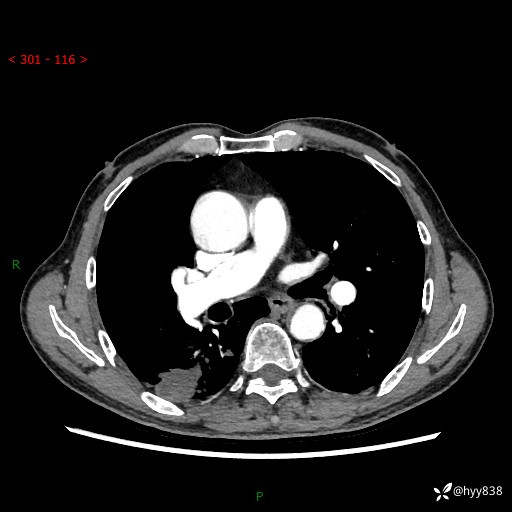

老年男性,发现右下肺结节3天。结节+卫星灶,似曾相识---结果公布~

简要病史:患者3天前于我院常规体检时行胸部CT提示“右下肺结节35mm*24mm”,自觉无发热、咳嗽、咳痰,无胸痛、咯血、气促加重,无声嘶、吞咽困难,无乏力、盗汗、体重减轻等不适。为求进一步诊治,入我院求诊,门诊以“右下肺结节待查”收入我科。患者3天前于我院常规体检时行胸部CT提示“右下肺结节35mm*24mm”,自觉无发热、咳嗽、咳痰,无胸痛、咯血、气促加重,无声嘶、吞咽困难,无乏力、盗汗、体重减轻等不适。为求进一步诊治,入我院求诊,门诊以“右下肺结节待查”收入我科。 起病以来,患者精神、食欲、睡眠可,体力稍差,大小便正常,体重无明显变化。

辅助检查:CT

临床诊断:肺结节

增强